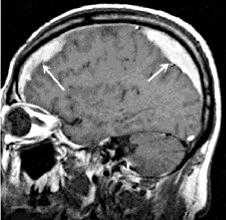

По локализации во внутричерепном пространстве выделяют:

- эпидуральные гематомы — располагаются между внутренней поверхностью костей черепа и твёрдой мозговой оболочкой;

- субдуральные — локализованы между твёрдой мозговой оболочкой и веществом головного мозга;

- внутримозговые гематомы — залегают в веществе головного мозга.